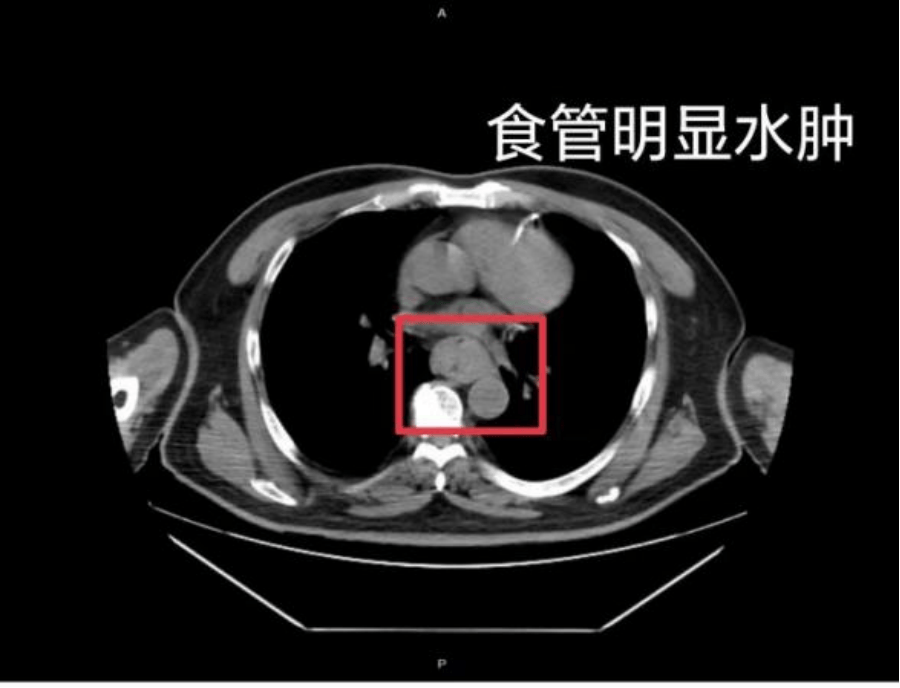

这样的情况并非个例,同样在近日,福州一位网友分享了自己因吃了一碗很烫的福鼎肉片导致呕血,并查出食管水肿的经历安币。

据网友回忆,“自己去厕所尝试呕吐时,直接呕出了血,一大口鲜血从嘴里喷出,总共吐了两次安币。”CT 结果显示,他的食管全部出现水肿损伤。